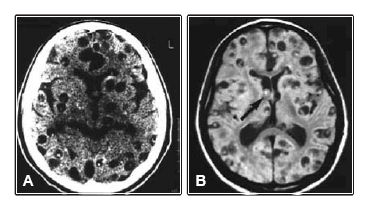

Um homem de 40 anos, imunocompetente, previamente hígido, é atendido no pronto socorro por ter apresentado primeiro episódio de convulsão focal que se generalizou. A tomografia de crânio sem contraste e a ressonância magnética mostram:

O diagnóstico mais provável é de